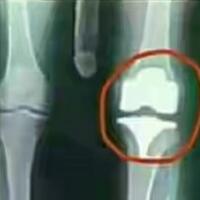

ssttttt....dulu dia pernah operasi lutut https://s.kaskus.id/images/2018/08/07/10258705_20180807011119.jpg :wakaka itu ulilnya kenapa ikut ke rontgen :ngacir2